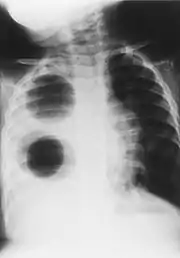

| Chest radiograph of a woman with unilateral pulmonary agenesis | |